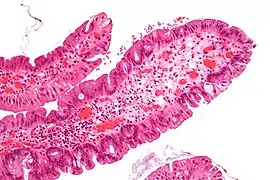

Peutz-Jeghers Polyp All digestive tract Smooth muscle bundles between nonneoplastic epithelium, "Christmas tree" appearance No

Micrograph of a Peutz–Jeghers colonic polyp – a type of hamartomatous polyp. H&E stain.